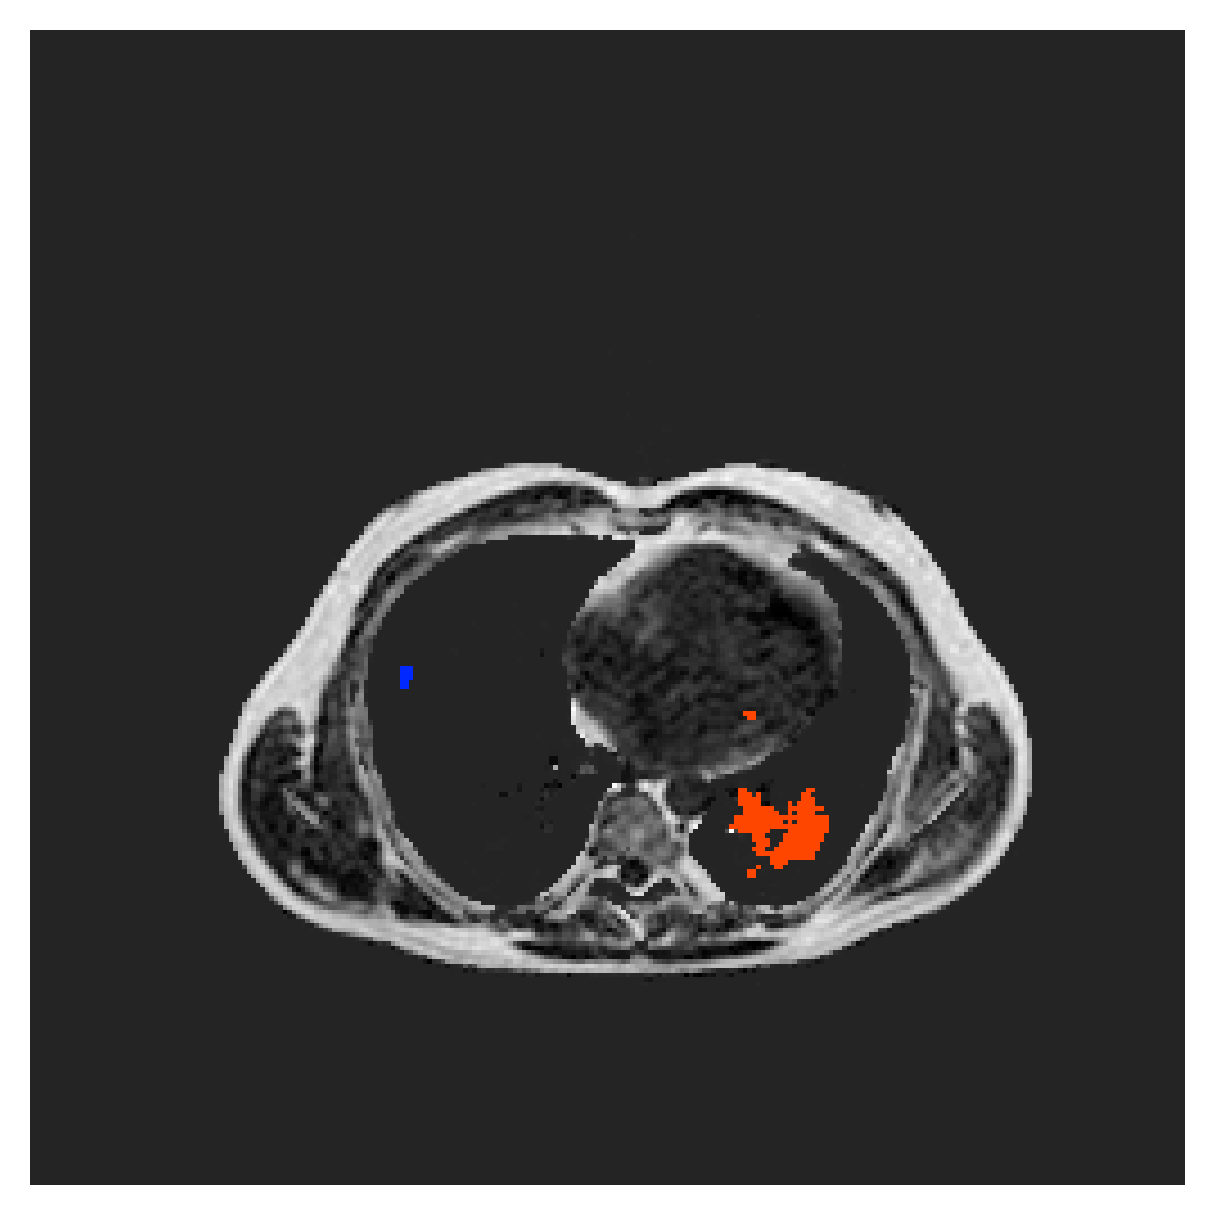

5.2 Abdominal organ segmentation

Using 2D distance maps

In Table 3, the average DSC and HD95 results are shown (both using 2D and 3D distance maps) for the task of abdominal organ segmentation in POEM data (for boxplots see figures 8 and 9). We see that training with and (with distances calculated on 2D slices) performs comparably, while using and produces lower scores in both DSC and HD95 metric. On this dataset, the CRF-loss is able to compete with the boundary loss-based training strategies, even outperforming them on most classes. Most notably, all models trained with boundary loss appear to have a hard time segmenting the liver. We hypothesize this may be due to extremely severe class imbalance, as the liver covers a very large area compared to the rest of the classes. It is thus also more strongly affected by undersegmentations.

According to the validation curves in Figure 7, training on this dataset is less stable, and slower, than on the ACDC one, for all methods. Using Euclidean or MBD maps appears to reach full-supervision scores, while the other methods lag behind. However, due to the long computation times on 3D data from the POEM cohort, these curves now show the evolution of the 2D Dice, which is less representative of the true success of the methods.

Using 3D distance maps

Inspecting the values of training with on distance maps computed in 3D from Table 3, we notice that the results generally improve over values achieved by using 2D distance maps. Most notable decreases are visible in HD95 values, as using volume-calculated distance maps provides more global information and additionally penalizes spatially unreasonable segmentations. The methods based on are now able to compete with the CRF-loss, in particular the one.

In Figure 10, the validation curve evolution is plotted. Comparing it to the one with using 2D-computed distance maps, in Figure 7, we see that the curves for all the methods training with improve, with the exception of based one. The lack of improvement here could be attributed to the MBD bleeding through object boundaries (due to noise) and propagating low distances further away in the volume, causing under-penalization. This is also suggested by the degradation in performance from 2D to 3D maps in Table 3. But at the same time, it allows for better segmentation of large and/or elongated (homogeneous) objects, which is also confirmed by the large improvement of liver segmentation scores in Table 3.

5.2.1 Qualitative comparison

In Figure 11 and 12 we show the same random slices in cases of calculating the boundary loss on 2D- and 3D-based distances, respectively. Comparing the two figures again indicates that the intensity-aware distances offer most improvement when calculated in 3D over 2D. The exception here is the MBD, which seems to even slightly degrade for most classes.